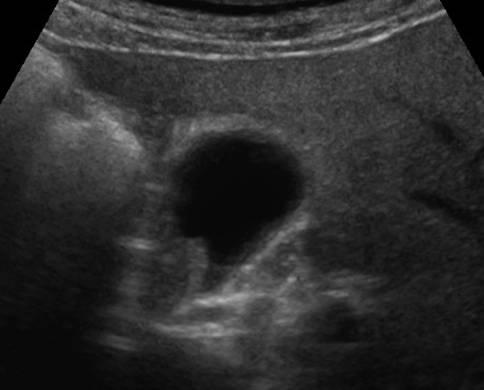

Ung thư túi mật

» Thông tin: Nam giới – 75 tuổi.

» Lâm sàng: Đau mạn sườn phải.